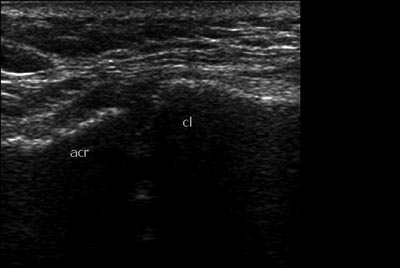

виды физиотерапии, мази без эффекта. Был проведен повторный Rg. На УЗИ я

выявила расширение

АКС до 15 мм, (на здоровой стороне суставная щель до 5 мм), содержимое

неоднородное, имеется

неровность дистального конца ключицы. Признаки разрыва

акромиально-ключичной связки.

Целостность сухожилий ротаторной манжетки сохранена. Выпота в сумках

нет. Описание